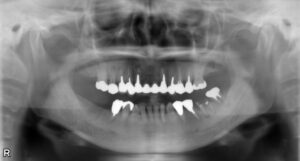

大臼歯2本欠損症例

BEFORE AFTER 43歳女性/上下2本欠損/インプラント埋込手術 【治療内容】 右上第二大臼歯の被せ物が外れてし…